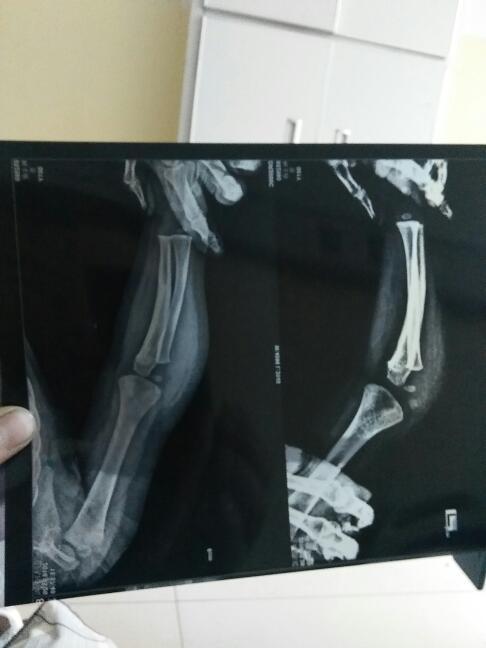

一岁半小孩胳膊肘摔伤,有小碎片必须手术吗 点击展开 匿名用户 2016-05-27 02:54 满意回答 这种情况应该及时手术治疗,避免遗留后遗症。 chenli2909 2016-05-27 06:57 宝宝知道提示您:回答为网友贡献,仅供参考。 相关问题 小孩子3岁摔伤了胳膊肘能吃云南白药吗? 小孩一岁胳膊肘摔伤麻烦业内专业人士帮我看看 小孩现打狂犬疫苗期间昨日摔伤胳膊肘肿疼怎么办